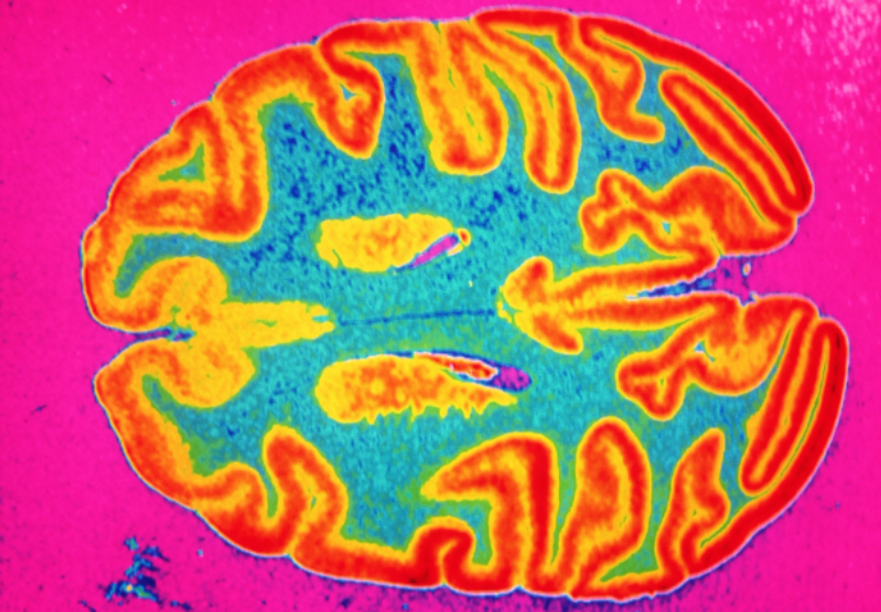

Namun, pemindaian otak sekarang menunjukkan bahwa bahkan kasus ringan COVID-19 dapat mengecilkan bagian otak, menyebabkan perubahan fisik yang setara dengan usia satu dekade. Persisnya mengapa masih menjadi misteri.

Beberapa bukti paling meyakinkan tentang kerusakan saraf setelah COVID-19 ringan berasal dari para peneliti Inggris yang menyelidiki perubahan otak pada orang sebelum dan sesudah tertular penyakit tersebut.

Hasilnya menunjukkan bahwa setelah empat setengah bulan infeksi moderat dengan virus corona, pasien (rata-rata) kehilangan antara 0,2 dan 2 persen volume otak mereka dan memiliki materi abu-abu yang lebih tipis daripada orang sehat.